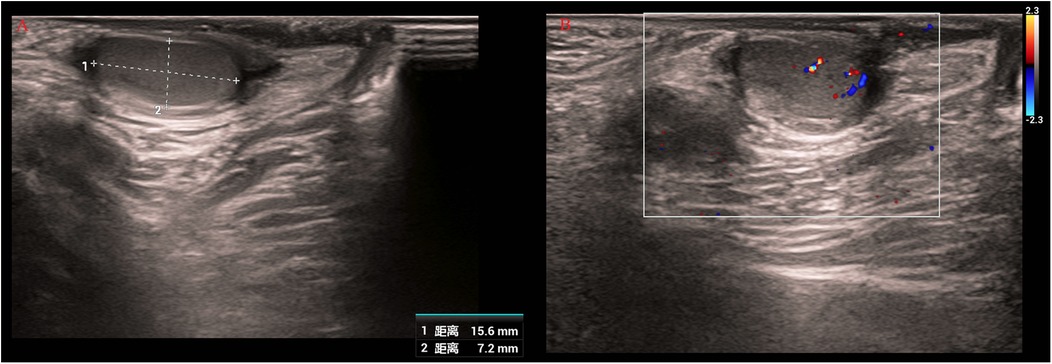

Background: Bilateral testicular tumors in infants are extremely rare. This case report describes synchronous bilateral mature teratomas complicated by torsion of an intra-abdominal undescended testis (IAT), and underscores the clinical importance of early diagnosis, timely surgical intervention, and fertility-preserving management, providing valuable reference for future cases. Case presentation: A 3-month-old boy presented with an empty right hemiscrotum. Imaging revealed a right intra-abdominal mass (22.8×15.9×21.3mm) and left testicular lesion (7.1×3.9×7.0mm). Serum alpha-fetoprotein was within normal limits for age, suggesting benign disease. Laparoscopy confirmed a torsed necrotic right testicular mass, managed by orchiectomy. Left testis-sparing surgery excised a separate tumor. Histopathology confirmed bilateral mature teratoma. Hormonal profiles, including testosterone (0.81 ng/mL) and follicle-stimulating hormone (3.74 mIU/mL), as well as karyotype (46,XY), were normal. No additional therapy was required, as mature teratomas are benign. Postoperative alpha-fetoprotein levels normalized, with no recurrence at 6-month follow-up. Parental education regarding testicular examination is important for early detection of future abnormalities. Conclusions: Tumors associated with intra-abdominal undescended testes warrant urgent intervention due to torsion risk. Surgery preserving testicular tissue is recommended for bilateral benign teratomas to maintain fertility. Serial alpha-fetoprotein monitoring and ultrasound surveillance are essential postoperatively.